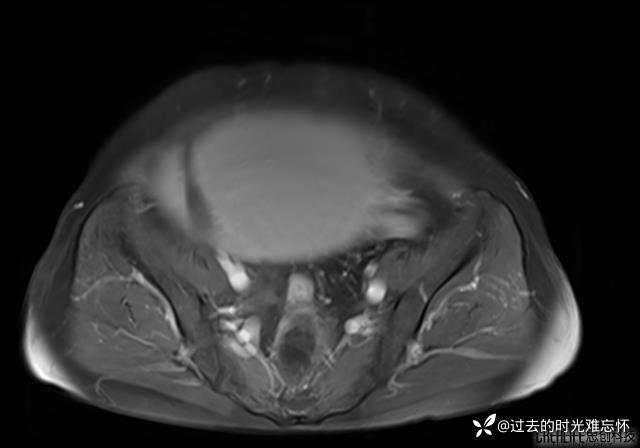

患者性别:女

患者年龄:65岁

主诉: 发现腹部隆起半年余。无其他明显不适。

浆液性囊腺瘤 (22)